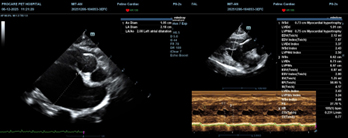

(A): LA/Ao = 2.08 (severe left atrial enlargement); (B): Interventricular septum and left ventricular free wall > 0.6 cm.

Regarding echocardiographic indices, statistically significant differences were observed for IVSd and LA/Ao, while LVPWd showed differences that did not reach statistical significance. For the LA/Ao ratio, a marked increase was observed across disease stages and was highly significant. This reflects the pathophysiology of HCM: left ventricular hypertrophy → reduced compliance → increased filling pressure → progressive left atrial enlargement over time. The LA/Ao value in stage C (2.55) greatly exceeded the reference threshold in the ACVIM consensus statement (2020), indicating chronically elevated filling pressures and high risk of pulmonary oedema and heart failure. This is consistent with Fuentes et al. (2020), who identified LA/Ao as the strongest predictor of congestive heart failure in HCM.

LVPWd but did not reach statistical significance (p = 0.052). This may be because more cats in the study exhibited an interventricular septal hypertrophy phenotype and were preferentially examined and diagnosed. According to Wess (2010), LVPWd is often not the predominant site of hypertrophy in early to moderate HCM. For IVSd, this index increased clearly across all three stages, and differences among stages were highly significant (p < 0.01). Specifically, from B1 to B2 there was a mild increase (0.63 to 0.70), and from B2 to C there was a marked increase (0.70 to 0.91). This indicates that interventricular septal hypertrophy was the dominant morphological pattern of HCM in this study population. This finding is consistent with Fuentes et al. (2020), who reported that IVSd > 0.9 cm is strongly associated with heart failure and arterial thromboembolism (ATE). A hallmark of HCM is asymmetric myocardial hypertrophy, most prominent in the interventricular septum. British Shorthair cats, in particular, tend to show a septal hypertrophy phenotype rather than predominant posterior wall thickening.

Pathophysiologically, HCM is characterized by left ventricular myocardial hypertrophy accompanied by secondary left atrial enlargement and could explain the strong association between VHS and disease progression portrayed in Table 7. Although VHS does not directly reflect myocardial wall thickness, it allows assessment of overall cardiac silhouette size on thoracic radiographs. Therefore, VHS tends to increase more markedly in later stages, when left atrial enlargement plays a major role in altering cardiac silhouette morphology (Sousa et al., 2025). The observation in stage B1 where VHS ranged from 7.80 to 8.20 (Table 7), is close to the normal reference range in healthy cats, and consistent with Sousa et al. (2025), who reported that thoracic radiography has low sensitivity for detecting early-stage HCM, because myocardial hypertrophy is not yet sufficient to cause obvious changes in cardiac silhouette. In stage B2, when hemodynamic alterations and cardiac remodelling become more evident, VHS increased slightly, in parallel with echocardiographic changes such as increased LA/Ao ratio and interventricular septal thickness. However, VHS may still not exceed clear diagnostic thresholds, highlighting its limitation in screening pre–heart failure HCM. In stage C, VHS increased markedly, and corresponds to the congestive heart failure stage, when severe left atrial enlargement, pulmonary oedema, or pleural effusion markedly alter cardiac silhouette appearance. This finding is consistent with reports by Ironside et al. (2021), in which high VHS values are considered a typical radiographic sign of heart failure in cats with HCM. With regards to echocardiographic indices, there was a significantly marked increase in LA/Ao ratio (Figure 3), reflective of the pathophysiology of HCM: left ventricular hypertrophy → reduced compliance → increased filling pressure → progressive left atrial enlargement over time. The LA/Ao value in stage C exceeded the reference threshold in the ACVIM Consensus Statement (2020), indicating chronically elevated filling pressures and high risk of pulmonary oedema and heart failure. This is consistent with Fuentes et al. (2020), who identified LA/Ao as the strongest predictor of congestive heart failure in HCM.